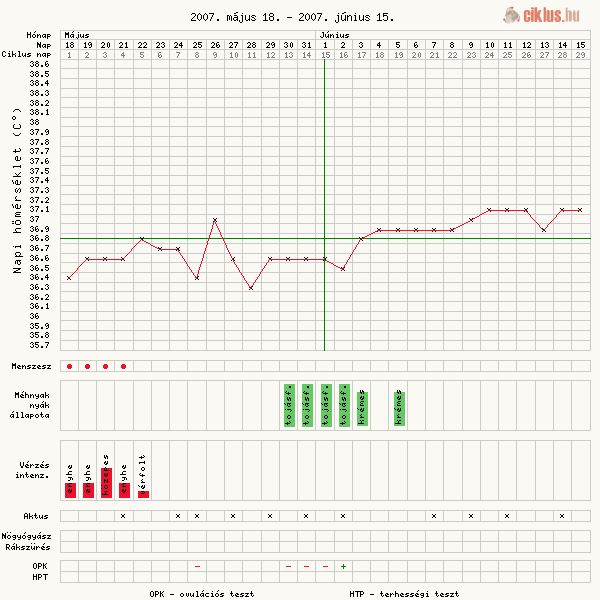

2. görbe

2. görbe